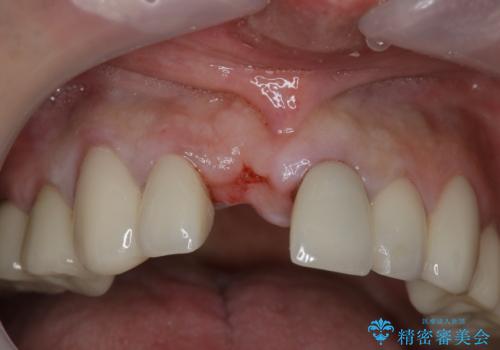

- 事故による外傷で前歯に歯根が真っ二つに折れてしまい、保存不可能となってしまった部分にインプラント治療を計画しました。

患者様のご要望もあり、審美性の確保ができる抜歯早期埋入→埋入後即時荷重という手術法を取りました。

近年、インプラントの素材や手術法の研究が進み、保存不可能となった歯牙に対して抜歯してすぐインプラントを埋入し、さらに直後から仮歯がを入れ噛むことができる【抜歯即時埋入】【即時荷重】という技法が確立されました。